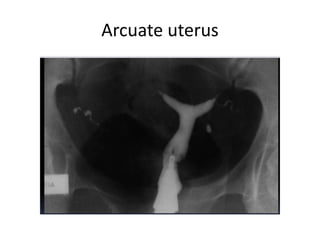

Arcuate uterus

• #19 Each mullerian duct- one side fallopian tube,1/2 uterus,1/2 cervix,1/2 upper part of vagina- mullerian agenesis- both mullerian ducts absent, Unicornuate- only one side mullerian duct present, uterus didelphis-failed fusion of paired mullerian ducts (2), uterus bicornuate- incomplete fusion of mullerian duct- 2 fallopian tubes,uterus,cervix-1 or2(bicornis unicollis, bicornis unicollis) single vagina, septate uterus(complete or partial) arcuate uterus- slight indentation of fundus, des induced reproductive tract abnormalities-t shaped uterus